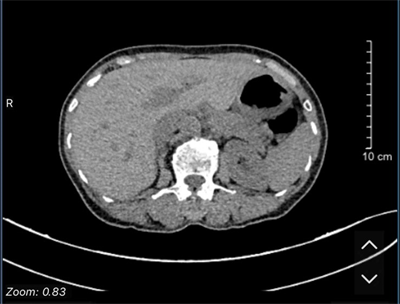

Ung thư biểu mô tế bào gan (hepatocellular carcinoma –HCC)  là loại ung thư thường gặp đứng thứ hai theo ghi nhận của Tổ chức Globocan Việt Nam năm 2022, ước tính mỗi năm có 24,502 trường hợp bệnh...